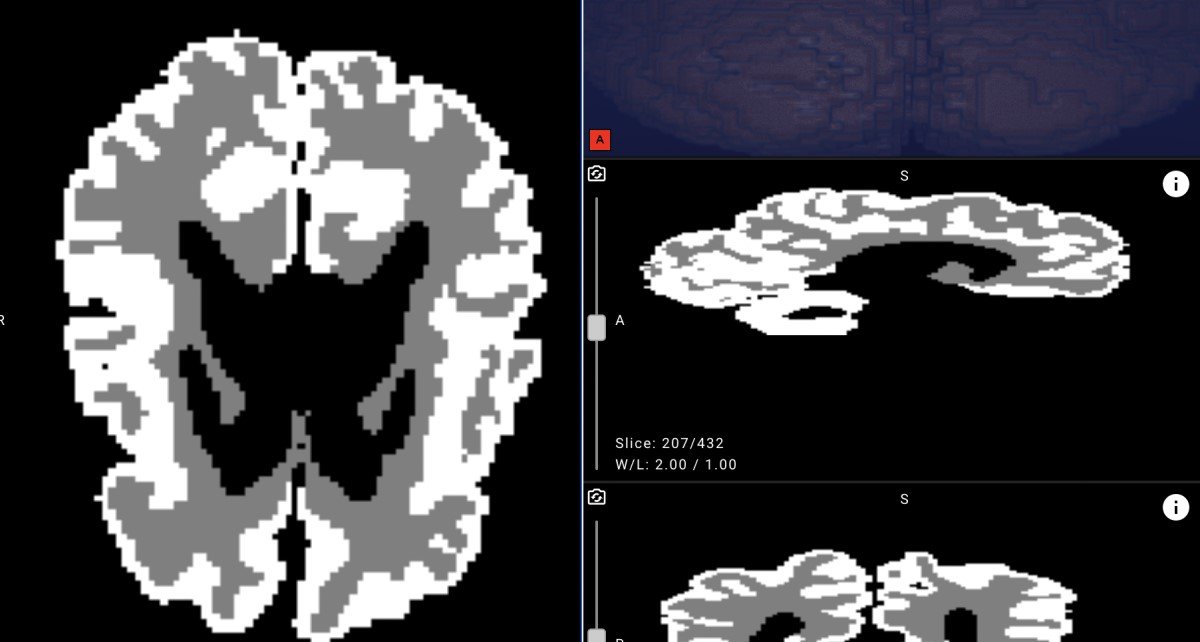

Яндекс представил первую в мире нейросеть, которая помогает врачам оценить развитие мозга малышей уже в первые месяцы жизни. Теперь на расшифровку результатов МРТ специалисту лучевой диагностики требуется не несколько дней, а всего несколько минут. Решение можно применять как вспомогательный инструмент при подозрении на детский церебральный паралич (ДЦП) и другие болезни центральной нервной системы для выбора лучшей тактики реабилитации пациента. Нейросеть протестировали специалисты Санкт-Петербургского государственного педиатрического медицинского университета (СПбГПМУ), и вуз готов делиться наработками с другими медучреждениями.

Технология позволяет значительно ускорить получение результатов исследования, чтобы принять решение о терапии, и оценивать развитие мозга в динамике. Это особенно важно при подозрении на патологию центральной нервной системы, в том числе ДЦП. Патология развивается в 2-3 случаях на 1000 новорожденных и является одной из основных причин детской инвалидности. Если болезнь удается выявить в первые месяцы жизни, то эффективность терапии повышается, а у пациента улучшается прогноз по восстановлению.

Новую систему разработали специалисты Центра технологий для общества Yandex Cloud и студенты ШАДа, совместно с Санкт-Петербургским педиатрическим медицинским университетом. Эксперты обучили нейросеть на 1500 обезличенных МРТ-снимков пациентов университета и на открытом наборе данных, предоставленном в рамках международного конкурса по сегментации МРТ-изображений головного мозга младенцев MICCAI Grand Challenge. Для автоматической разметки применялась модель BIBSNet (Baby Intensity-Based Segmentation Network). Для сегментации изображений применили две нейросети: ResNet и U-Net. Специалисты Yandex Cloud предложили архитектуру решения, протестировали и настроили веб-сервис. Позднее разработку планируют выложить в открытый доступ, чтобы её могли использовать в медицинских и других проектах по всему миру.